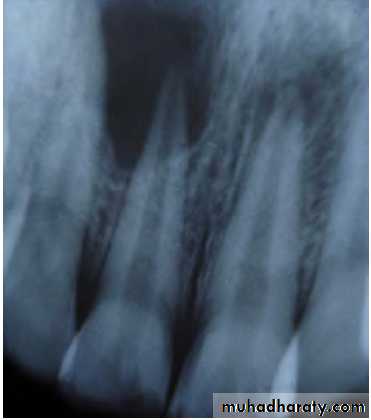

Radiographic Features

• Radiolucency at root and adjacent bone• Irregular shortening or thinning of root

• Loss of Lamina dura.